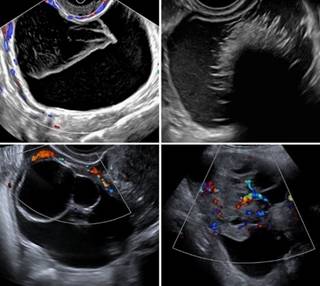

Ultrasound is the primary imaging modality of the female pelvis which allows adequate evaluation of most adnexal lesions using transvaginal and transabdominal technique. The O-RADS US lexicon uses terms supported in the literature and by the International Ovarian Tumor Analysis (IOTA) group to describe ovarian/adnexal lesions and assign a risk of malignancy. Imaging and clinical management recommendations accompany the risk assessment categories to optimize patient outcomes. An update to the O-RADS US system was made in November 2022 (O-RADS US v2022) and all governing documents (tables, lexicon, governing concepts, etc.) have been modified accordingly.